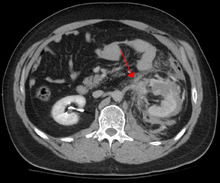

Blunt abdominal trauma

Blunt abdominal trauma (BAT) represents 75% of all blunt trauma and is the most common example of this injury.[4] 75% of BAT occur in motor vehicle accidents,[5] in which rapid deceleration may propel the driver into the steering wheel, dashboard, or seatbelt,[6] causing contusions in less serious cases, or rupture of internal organs from briefly increased intraluminal pressure in the more serious, depending on the force applied. Initially, there may be few indications that serious internal abdominal injury has occurred, making assessment more challenging and requiring a high degree of clinical suspicion.[7]

There are two basic physical mechanisms at play with the potential of injury to intra-abdominal organs: compression and deceleration.[8] The former occurs from a direct blow, such as a punch, or compression against a non-yielding object such as a seat belt or steering column. This force may deform a hollow organ, increasing its intraluminal or internal pressure and possibly lead to rupture.

Deceleration, on the other hand, causes stretching and shearing at the points where mobile contents in the abdomen, like bowel, are anchored. This can cause tearing of the mesentery of the bowel and injury to the blood vessels that travel within the mesentery. Classic examples of these mechanisms are a hepatic tear along the ligamentum teres and injuries to the renal arteries.

When blunt abdominal trauma is complicated by 'internal injury,' the liver and spleen (see blunt splenic trauma) are most frequently involved, followed by the small intestine.[9]